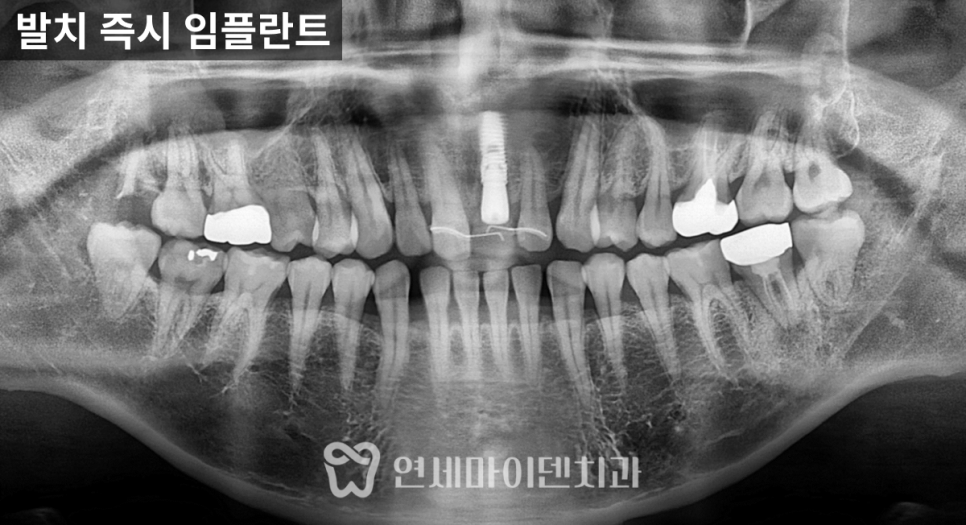

염증이 있어도 즉시 임플란트가 가능했던 이유

발치를 결정한 이후에는

즉시 임플란트 식립가능한지 여부를 판단해야 합니다.

뒤쪽 뿌리 부위는 뼈가 많이 소실되어 있었지만,

앞쪽 뿌리 부위에는 비교적 건강한 뼈가 남아 있었고

중간 부위에서도 일정 수준의 고정력을

확보할 수 있는 조건

이었습니다.

또한 아래턱은 하치조 신경관이 지나가는 부위이기 때문에

CT를 통해 정확한 위치를 계획한 뒤

발치와 동시에 임플란트를 식립했습니다.

치료 후 잇몸 회복 과정

임플란트 식립 시

초기 고정력이 충분히 확보되어

힐링 어버트먼트를 연결해

1차와 2차 수술을 동시에 마무리할 수 있었습니다.

실밥 제거 시점에는

기존에 있던 고름 주머니가 사라졌고,

잇몸은 비교적 빠르게

안정된 상태로 회복되는 모습을 보였습니다.

이후 한 달 경과에서도

염증 재발 없이 깨끗한 상태가 유지되었습니다.